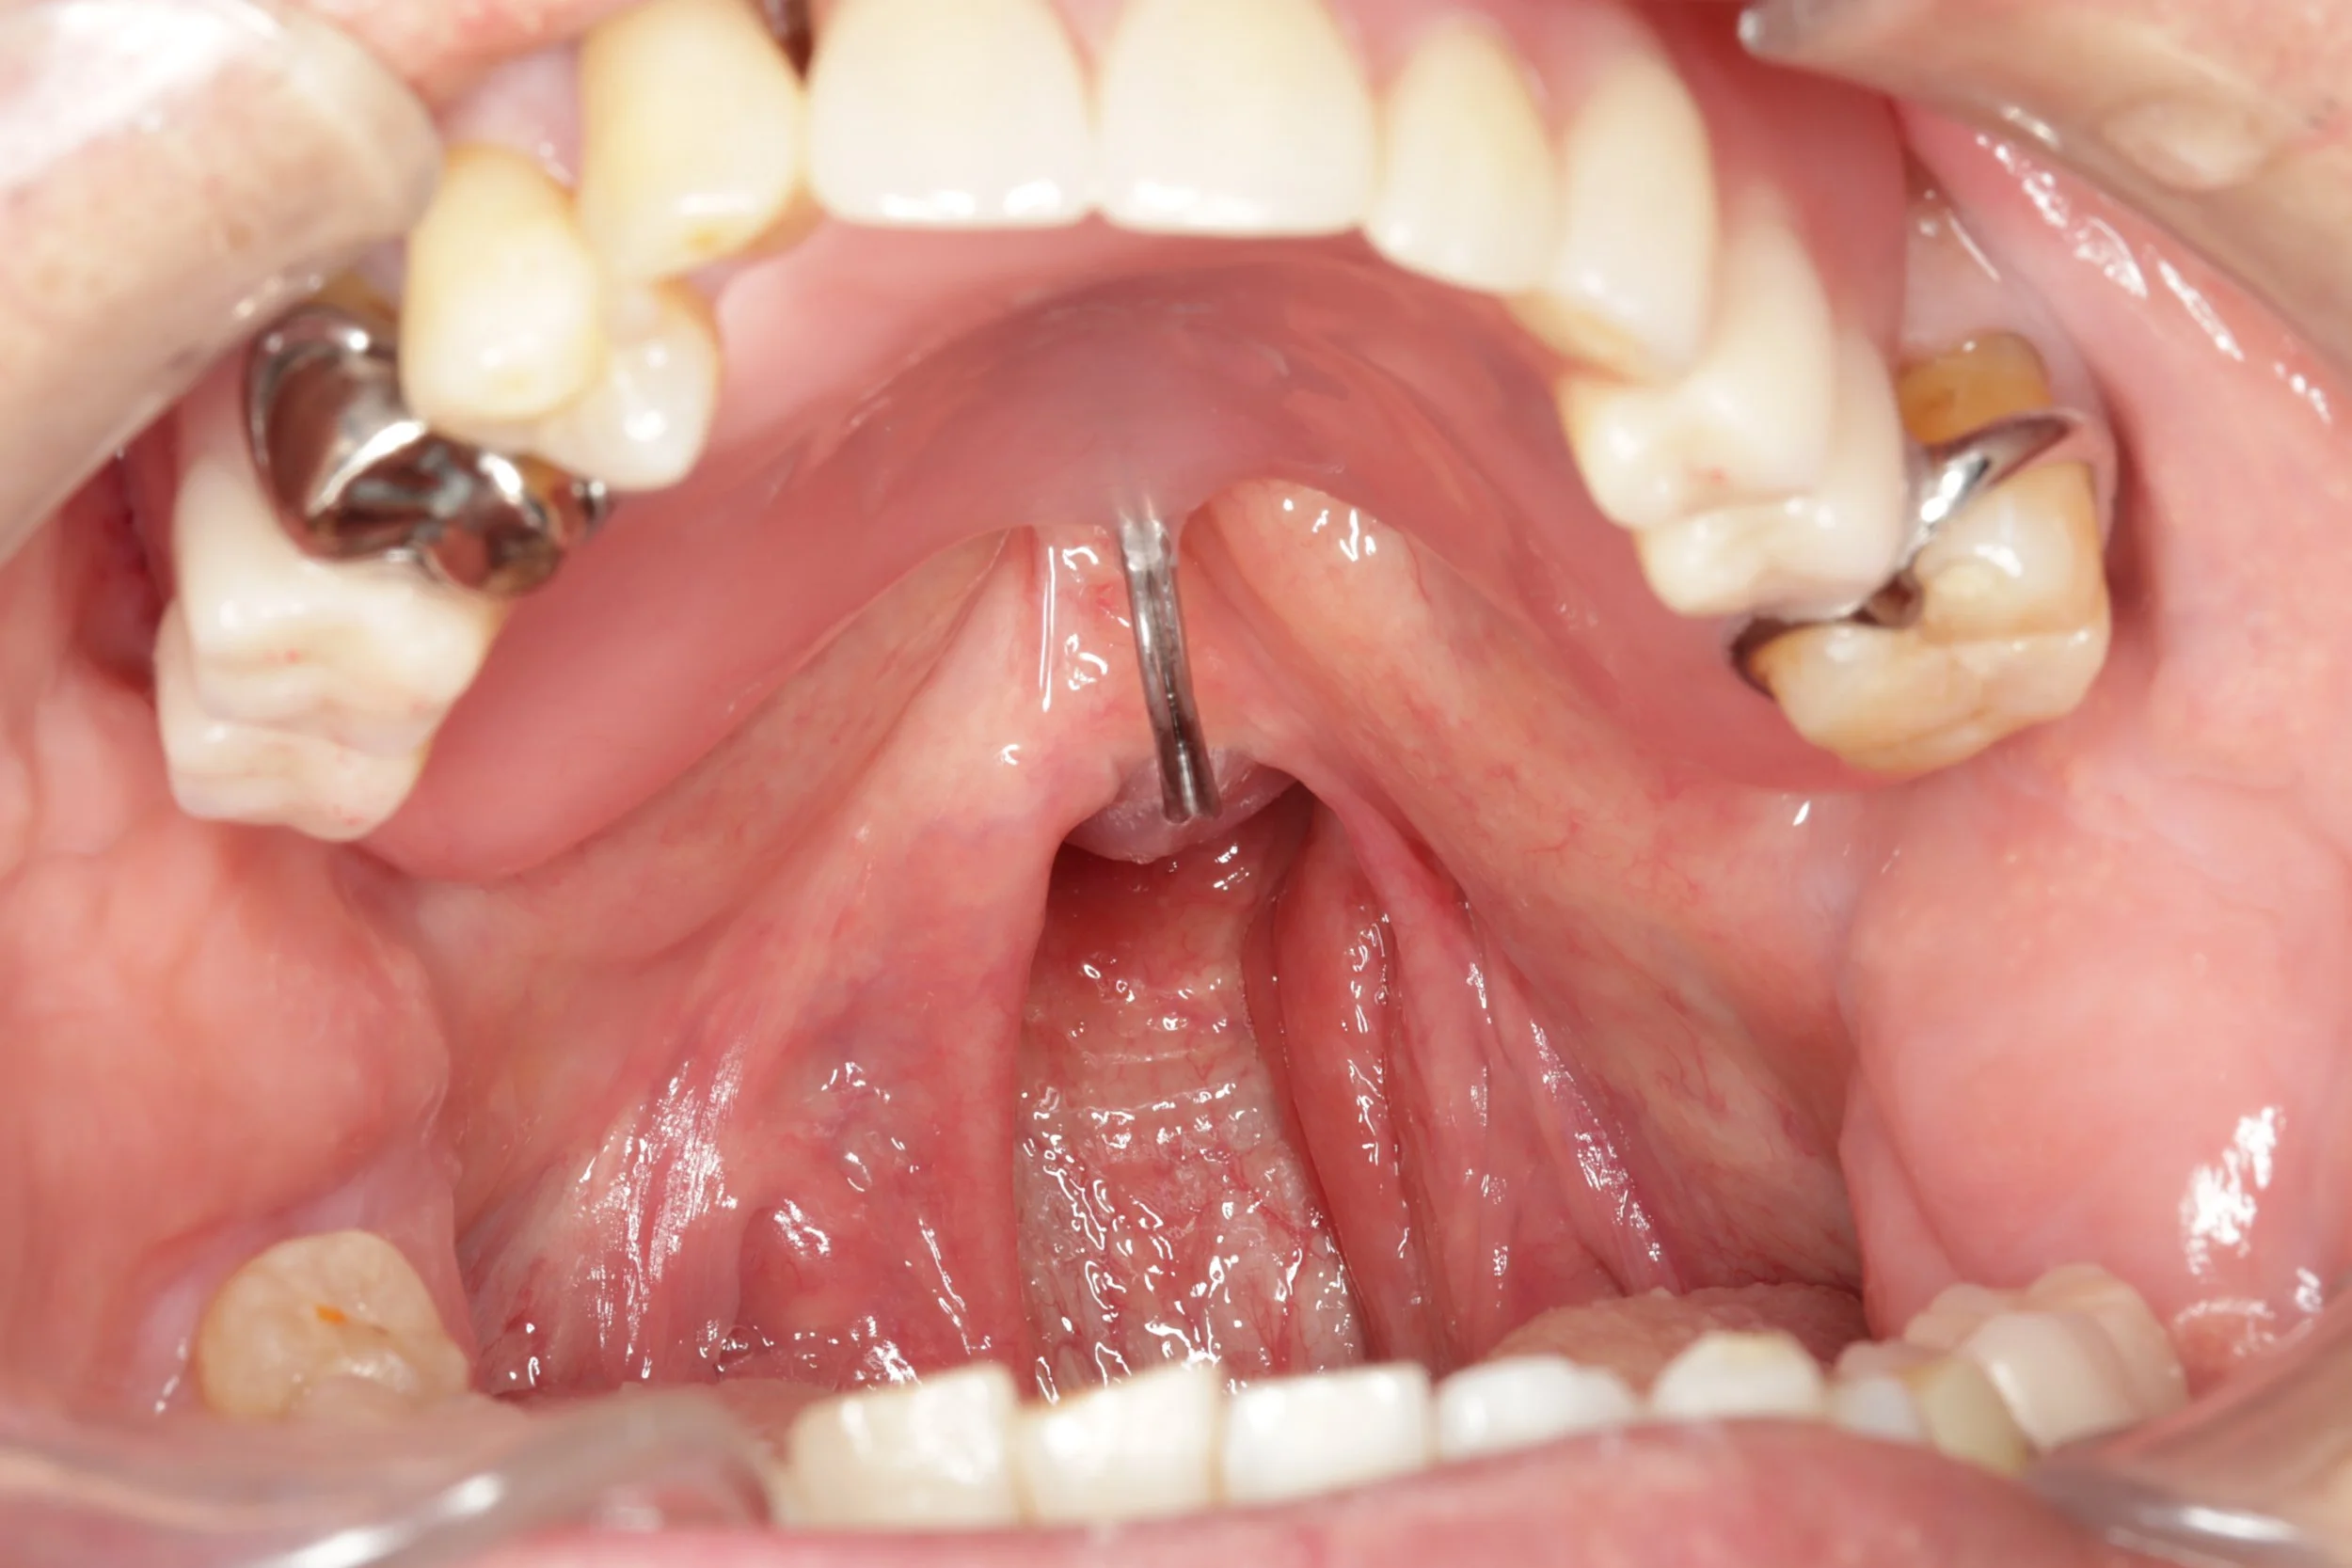

安静時の喉の状態

軟口蓋がリラックスしている状態で 喉とスピーチエイドの球体の部分には隙間があります。

鼻咽喉閉鎖機能時の状態

軟口蓋が動いて喉を閉鎖しようとするが閉鎖が不十分なところがあるので、スピーチエイドで補っている状態。

写真ではわかりやすくするため「あー」と声を出してもらいながら撮影しております。